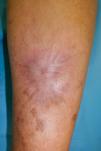

Placa exofítica con bordes bien definidos de 10×7cm, junto con nódulos violáceos en la zona circundante. El centro de la placa revela la presencia de úlcera con trasfondo de fibrina, rodeada por límites vegetativos, bordes mamilados y tejido friable. La lesión mostró induración y adherencia a las capas más profundas, con supuración serohemática.